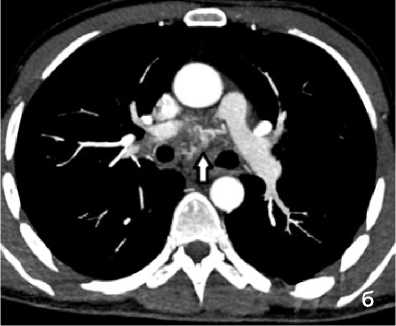

Рисунок 4. КТ грудной клетки с болюсным КУ (артериальная фаза), аксиальные срезы: а (лёгочный режим) – геморрагическое пропитывание в средней доле правого лёгкого (стрелка); б (средостенный режим) – расширение и извитость бронхиальных артерий (сосудистая мальформация – стрелка)

Figure 4. Chest CT with bolus contrast enhancement (arterial phase), axial slices: a (lung window) – hemorrhagic infiltration in the middle lobe of the right lung (arrow); б (mediastinal window) – dilation and tortuosity of bronchial arteries (vascular malformation – arrow)

При КТ-исследовании косвенным признаком состоявшегося ЛК является геморрагическое пропитывание лёгочной ткани в виде зоны неоднородного повышения плотности от «матового стекла» до мягкотканных значений с визуализаций просвета бронхов (рис. 4, а). Локализация пропитывания в большинстве случаев позволяет установить бассейн повреждённого сосуда. КТ-признаком продолжающего кровотечения является эктравазация контрастного препарата в виде гиперденсивных участков неправильной формы, появляющихся в артериальную фазу (при артериальном кровотечении) и увеличивающихся по размеру в последующие фазы КУ. КТ позволяет выявить не только признаки кровоизлияния, но и в большинстве случаев причину его возникновения (рис. 4, б).